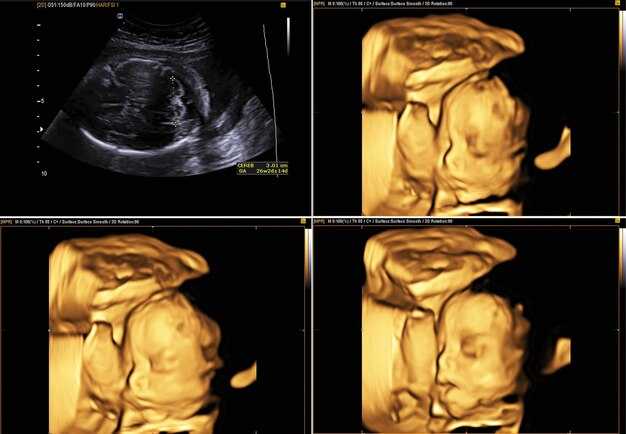

Клинические случаи: анализ результатов УЗИ

При интерпретации изображений важно учитывать побочные факторы и индивидуальные особенности пациента. В результате одного из исследований у пациентки 28 лет обнаружено образование, соответствующее желтоорганному циклу. Размеры структур составили 2,5 см и 3,0 см в диаметре, с четкими контурами и однородной эхогенностью.

Рекомендации включают динамическое наблюдение с повторным ультразвуковым исследованием через месяц для оценки стабильности образования. Если размеры увеличатся более чем на 1 см, следует рассмотреть дополнительные методы диагностики, такие как МРТ или КТ.

В другом случае, у женщины 35 лет выявлено кистозное образование с неоднородной внутренней эхогенностью, размером 4 см. Отмечено наличие перегородок и мелких кальцинатов. Это может указывать на персистирующие функциональные кисты или же на возможный рак яичника.

Рекомендуется направить пациентку на консультацию к онкологу и провести дополнительные исследования, включая анализы на опухолевые маркеры. Мультидисциплинарный подход обеспечит всеобъемлющее понимание ситуации.